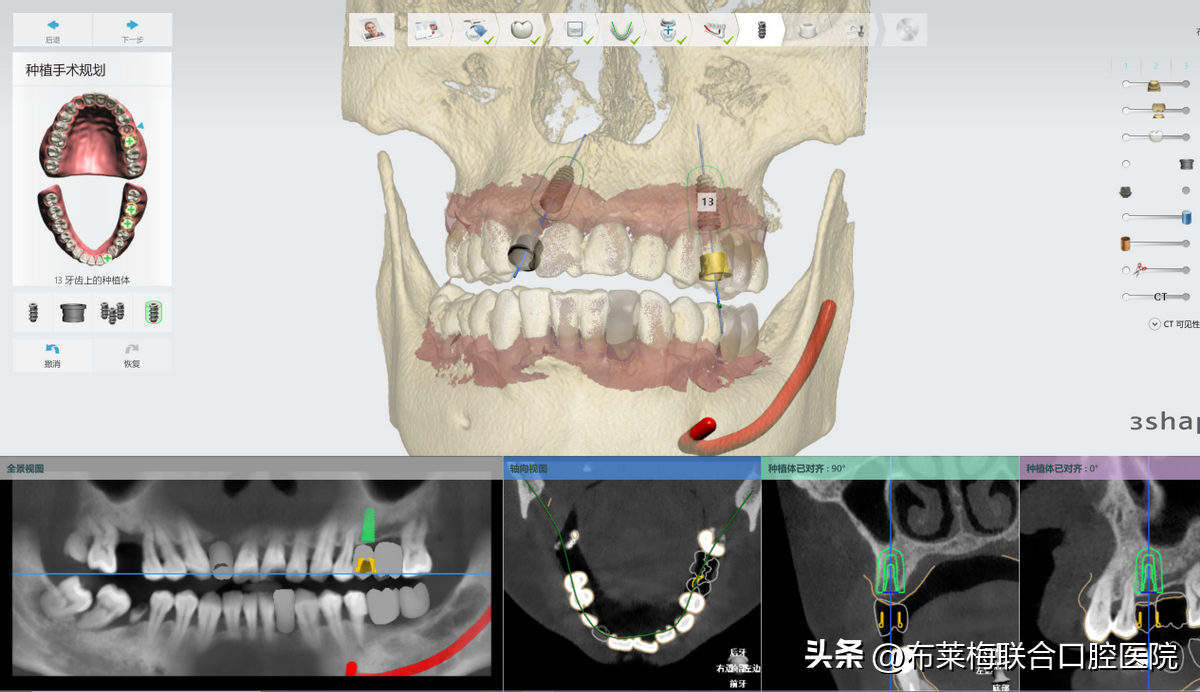

數(shù)字化種植牙技術(shù)可以讓醫(yī)生提前設(shè)計出調(diào)節(jié)方案,再在計算機(jī)上模擬生成術(shù)后果圖供患者和家屬確認(rèn)。

真真實(shí)實(shí)的在大屏幕上看到自己的方案,以及種植操作時的過程,植體走哪里安進(jìn)去,有沒有避開神經(jīng),都是一清二楚。不僅放患者安心,更讓陪同的家屬放心

數(shù)字化種植牙技術(shù)簡單來說,就是手術(shù)中提前預(yù)判好術(shù)中可能會出現(xiàn)的風(fēng)險,同時把誤差減少到毫米,提前讓醫(yī)生和患者知悉確認(rèn)的。降低了手術(shù)的風(fēng)險系數(shù),也可以讓患者稍微放松心情。恐懼是源于未知,那將這些信息都提前告知患者和家屬,自然對手術(shù)也就不會過度緊張

數(shù)字化種植牙利用計算機(jī)計算出牙骨組織情況,準(zhǔn)確測量種牙的位置、角度、深度,做到量體裁衣

不管是醫(yī)生操作的準(zhǔn)確度還是患者的過程中的舒適度都是大大提高了的。